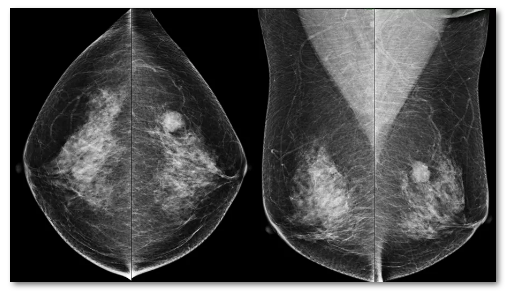

主要用于乳腺疾病的诊断和筛查,其操作简单,价格相对便宜,特别是对乳腺内钙化非常敏感,能够发现2mm以下的钙化灶,而钙化被认为是早期乳腺癌的重要征象之一。目前,乳腺X线检查被用于45岁或50岁以上女性的筛查手段。